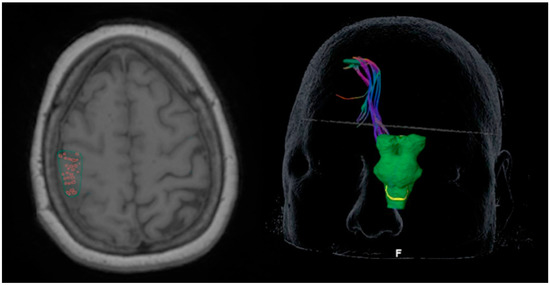

2.1. Transcranial Magnetic Stimulation

2.2. Diffusion Tensor Imaging

2.3. Perioperative Overlays